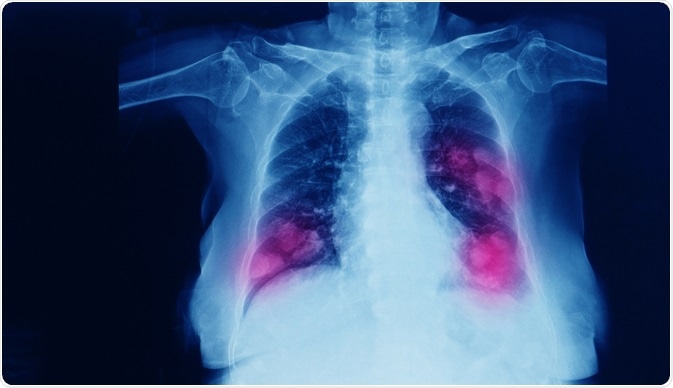

Image Credit: Yok_onepiece/Shutterstock.com